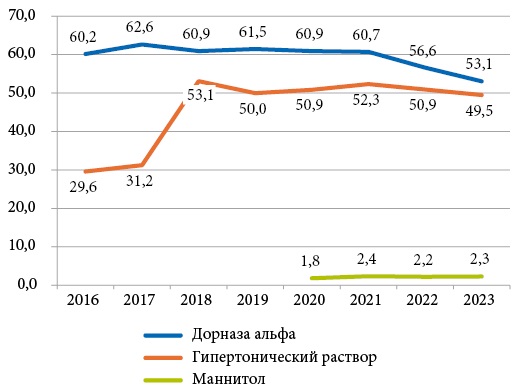

Проведен анализ применения муколитических препаратов по данным национальных регистров пациентов с муковисцидозом (МВ) в странах Европы, США, Канады, Австралии и России. Муколитическая терапия является основным компонентом терапии пациентов с МВ. Муколитические препараты применяли у пациентов всех возрастов. Дорназу альфа назначали большему числу пациентов по данным всех регистров. В России препарат доступен для всех пациентов благодаря программе ≪14 высокозатратных нозологий≫ и выпускаемому в России биоаналогу дорназы альфа. По данным регистров, дорназу альфа чаще, чем в других странах, применяли в России — до 95,8% в 2019 г., причем 25,9% пациентов получали вторую дозу интраназально (в 2023 г.). В США дорназу альфа назначали до 90% пациентов, в Австралии — до 60%, в Канаде — до 52% взрослых пациентов, в странах Европы препарат получали более 50% пациентов. Из быстрых муколитиков преобладали назначения ингаляций гипертонического раствора, который в США получали до 77% пациентов, в России — до 72,7%, в странах Европы — до 52,3%, в Австралии — до 45,4%, в Канаде — до 41,6% взрослых пациентов с МВ. Ингаляции маннитола применяли в единичных случаях — преимущественно в подростковом возрасте (до 15,7% подростков с МВ Австралии в 2020 г.). В последние годы во всех странах отмечена тенденция к незначительному снижению потребности в муколитических препаратах, что, вероятно, связано с применением CFTR-модуляторов.